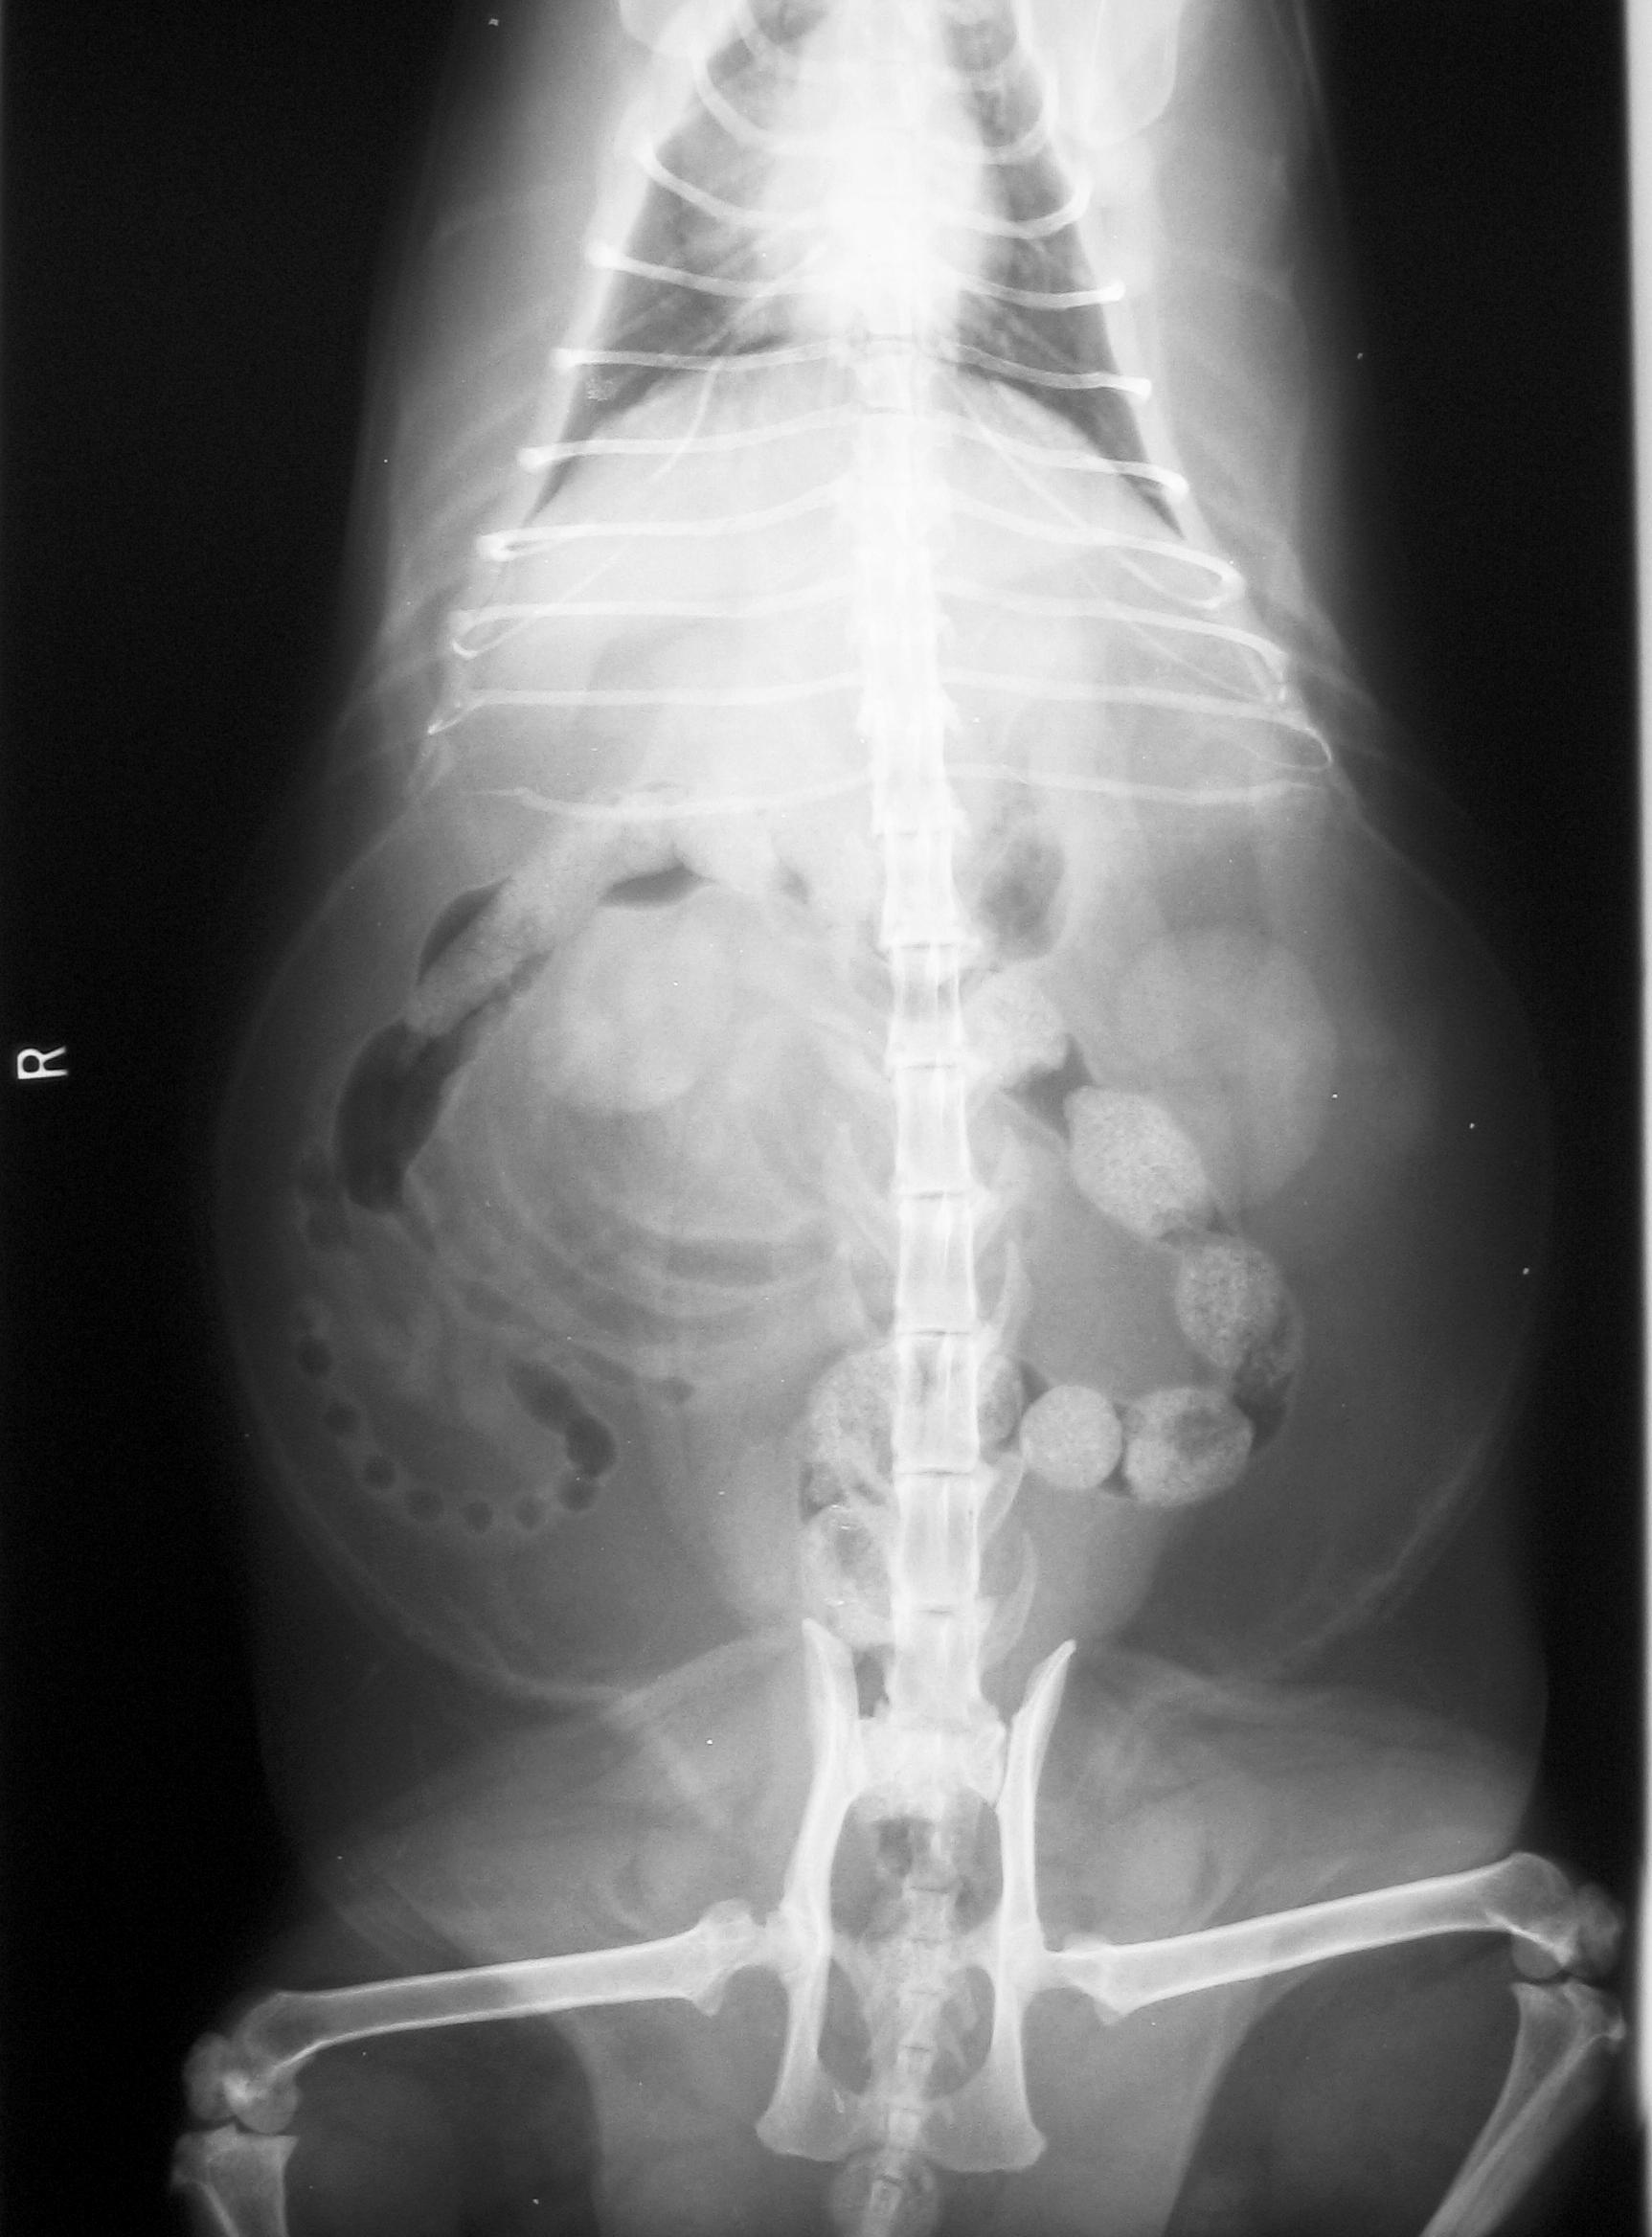

Rayos X